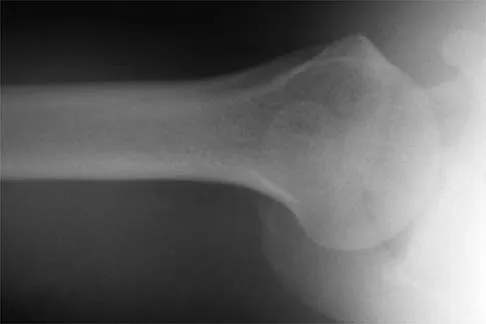

A 24-year-old baseball pitcher reports pain over the posterior aspect of his shoulder that occurs only during throwing. He notes that the discomfort is greatest during the late cocking and early acceleration phases. Examination reveals localized tenderness with palpation over the external rotators and posterior glenoid. Radiographs are shown in Figures 38a through 38c. What is the most likely diagnosis?